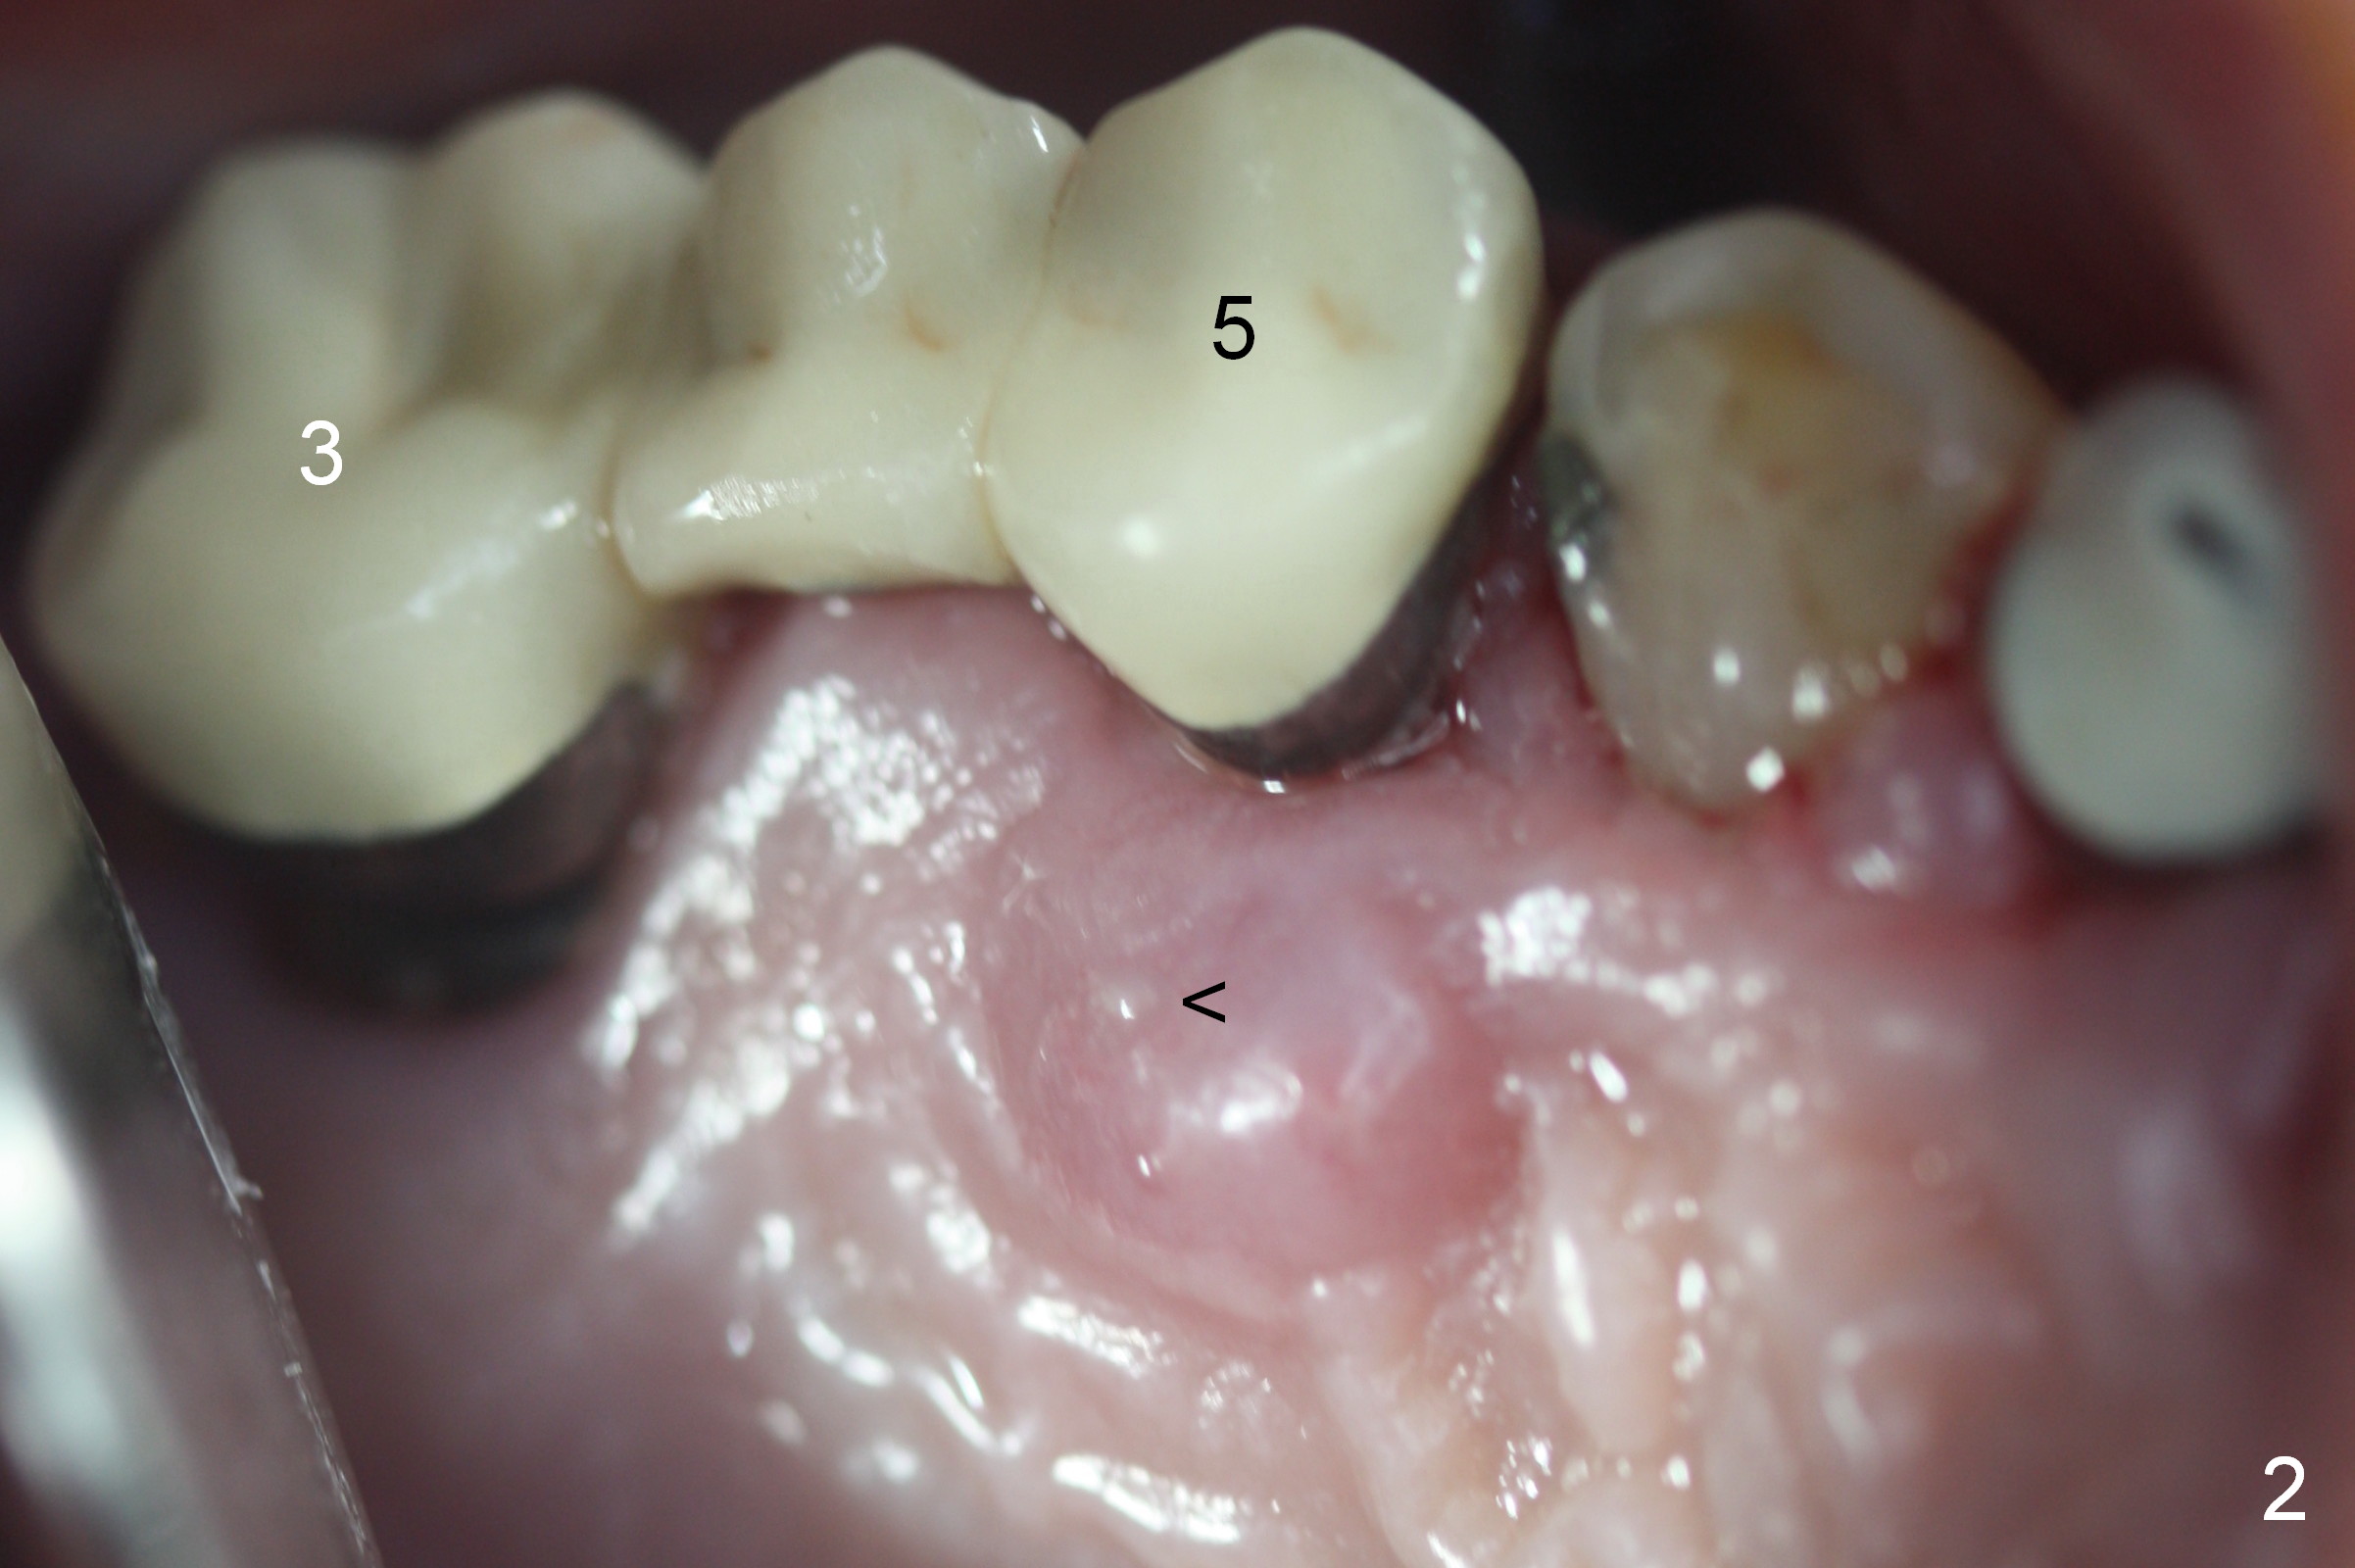

Preop photos show generalized gingival hyperplasia (hypertension med (Amlodipine, Calcium Channel Blocker), Fig.1 *), palatal (Fig.2<) and buccal (Fig.3 B) abscesses originated from the tooth #5. There is a smaller abscess buccal to the tooth #3 (not shown). After extraction, the buccal and palatal plates of the teeth #3 and 5 are found basically non-existent. When taps are placed, large socket defects are evident (Fig.4 *). In addition to sinus lift at #3 (Fig.5 black *), mineralized cancellous and cortical allograft (.5-1 and 1-2 mm) is placed around the implants with healing screws in place (white *). After the healing screws are removed and cemented abutments are placed, more allograft is packed (Fig.6-8 *). Closing the "dead" space in step may prevent immediately postop infection and peri-implantitis.